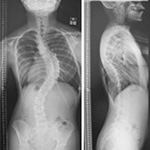

脊椎

Spine

• 1)脊柱変形

• 2)脊椎変性疾患(腰椎椎間板ヘルニア、腰部脊柱管狭窄症、頚髄症、後縦靭帯骨化症等)

• 側彎症をはじめとする脊柱変形の手術成績の検討